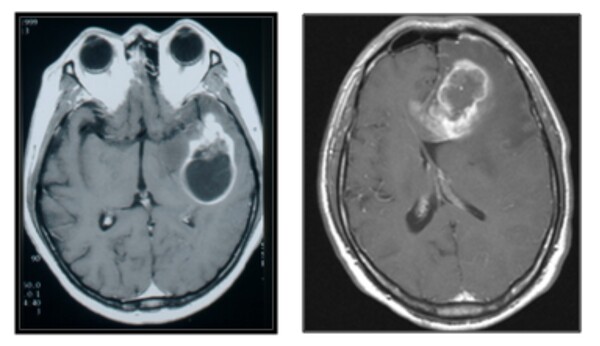

![[자료3] 양성뇌종양과 악성뇌종양](https://cdn.healthlifeherald.com/news/photo/202507/2798_4816_1038.jpg)

양성과 악성, 치료의 차이점은?

양성 뇌종양은 성장 속도가 매우 느리며 수술로 완치가 가능하다. 대표적으로 뇌수막종, 뇌하수체 선종, 신경초종 등이 있다. 반면 악성 뇌종양은 뇌 조직을 침범하며 빠르게 진행된다. 그중 교모세포종은 가장 치명적인 유형으로 평균 생존 기간이 치료를 받아도 약 1년 정도에 그친다. 따라서 조기 진단과 적극적인 치료가 중요하다.